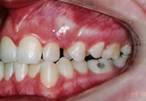

Paciente com 7 anos de idade, dentes permanente largos e mordida cruzada posterior direita. Se não tratado, poderá ter assimetria facial no futuro (face do lado direito mais volumosa que o esquerdo.